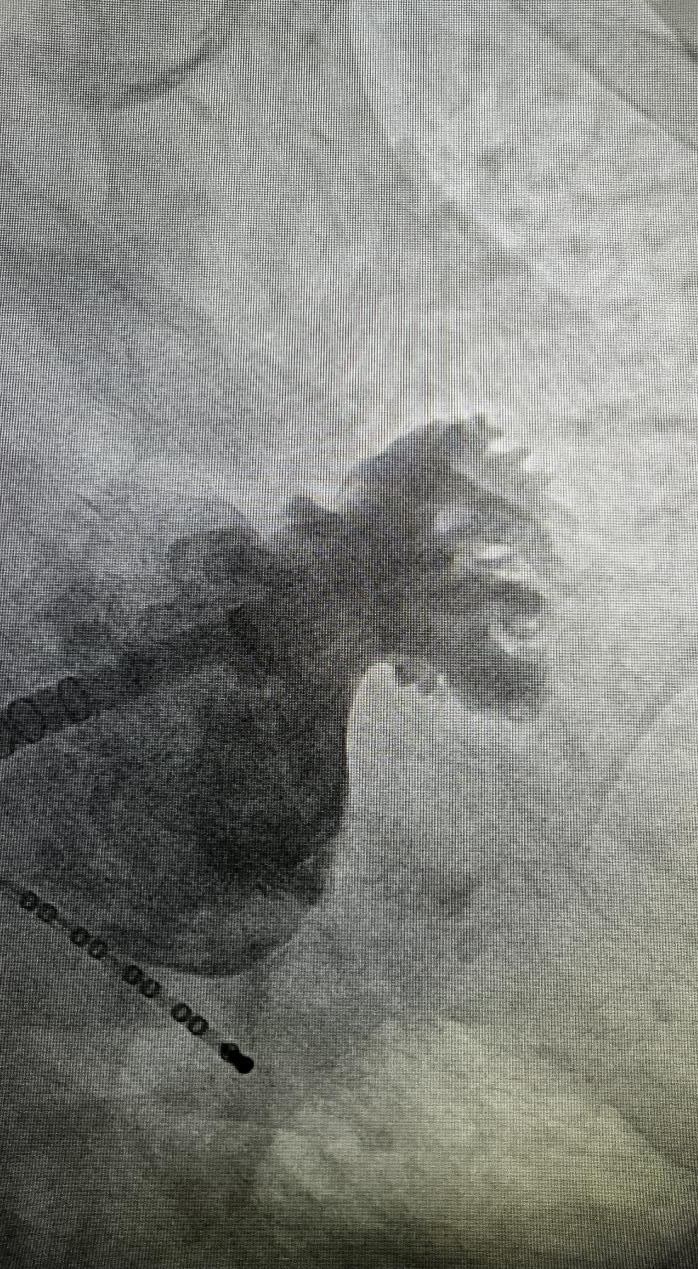

车星请心内科会诊,心血管内科主任阮中宝告诉老人,当房颤发生时,血液容易在左心耳内形成血栓,血栓随着心脏泵血会流向全身,造成不同部位动脉血管被堵,可以把左心耳封堵掉。

听了阮中宝主任的一番科普后,老人要求做左心耳封堵手术。

为了斩草除根,经过综合考虑,阮中宝主任治疗团队决定为老人做房颤一站式手术,即房颤导管消融和左心耳封堵一起完成的手术,同时解决房颤和左心耳的问题。